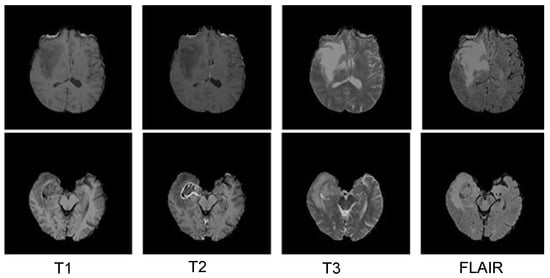

3.5.1. BraTS 2018 Dataset

4.3. Results Evaluation Using BraTS 2018 Dataset